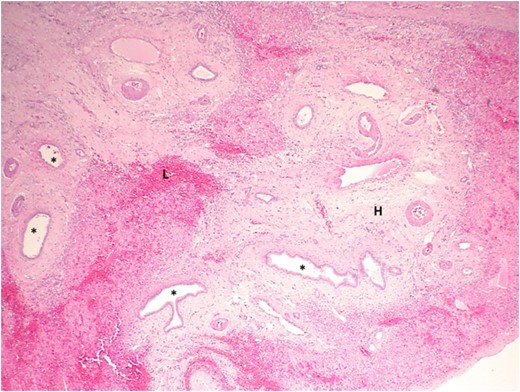

Low power view of the hepatic cyst (asterisk) using hematoxylin and eosin staining. The cyst wall is composed of loose collagenous tissue lined by a single layer of cuboidal cells (arrow) representative of biliary type epithelium. Ectatic BD are seen in the adjacent liver parenchyma.

Photograph showing a high-power view of liver parenchyma adjacent to the cyst using hematoxylin and eosin staining. The liver parenchyma contains several ectactic BD (asterisk), some with focal branching. The stroma is densely hyalinized (H) and contains a dense lymphocytic infiltration (L).